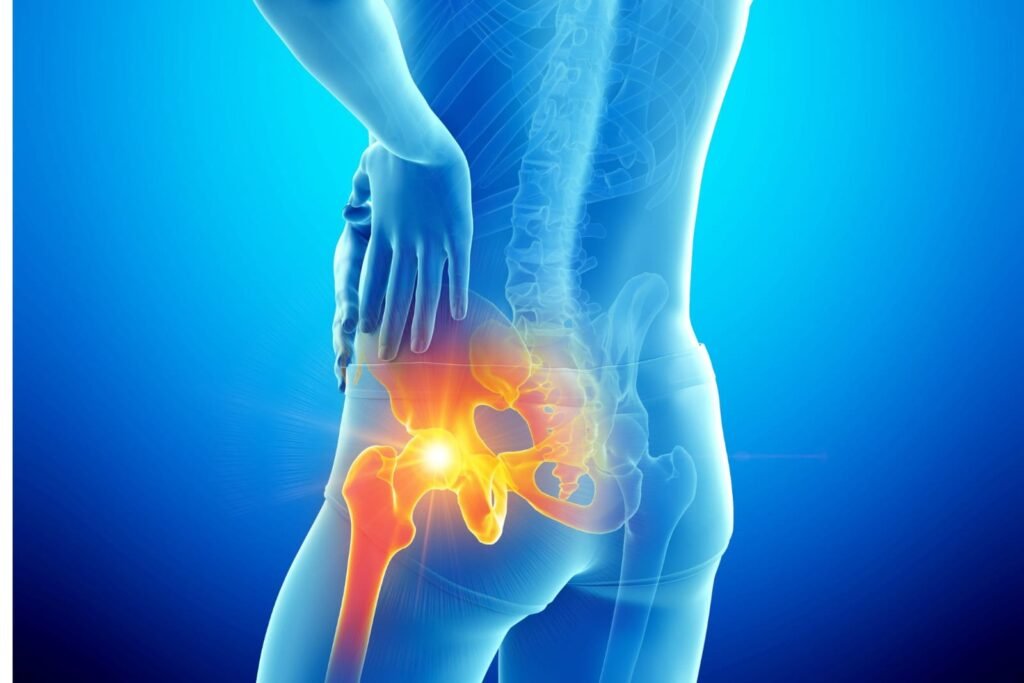

Hip replacement surgery relieves severe pain caused by arthritis, fractures, or joint degeneration by replacing the damaged joint with durable implants. It restores mobility and improves overall quality of life. Revision hip replacement corrects problems with a previous implant using advanced reconstructive techniques. Both procedures aim to provide stability, comfort, and long-term joint function.

Primary hip replacement is a highly effective procedure for treating severe arthritis, hip joint damage, and fractures. The procedure involves replacing the damaged ball-and-socket joint with high-quality implants that mimic natural movement. Patients typically experience significant relief from pain, improved mobility, and enhanced overall quality of life.

Revision hip replacement is performed when an earlier implant wears out, loosens, or causes discomfort. This surgery is more complex and requires expert assessment, precise planning, and specialised reconstruction techniques. The goal is to restore stability, reduce pain, and rebuild proper hip alignment.